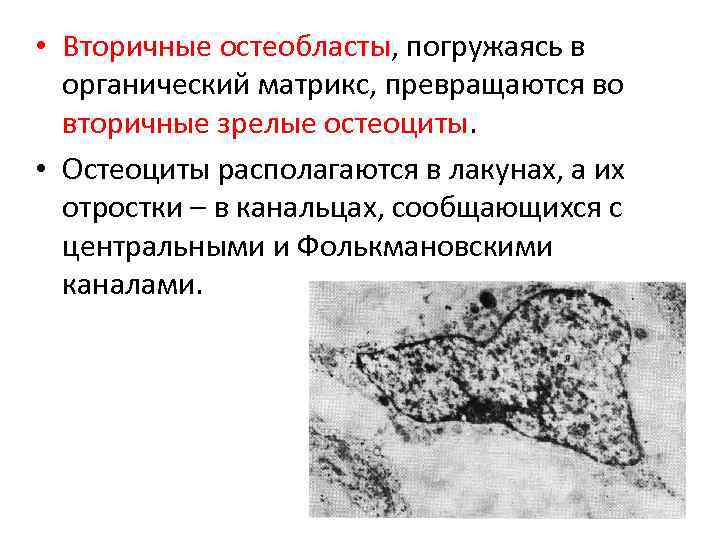

Структура грубоволокнистой костной ткани: наглядные примеры